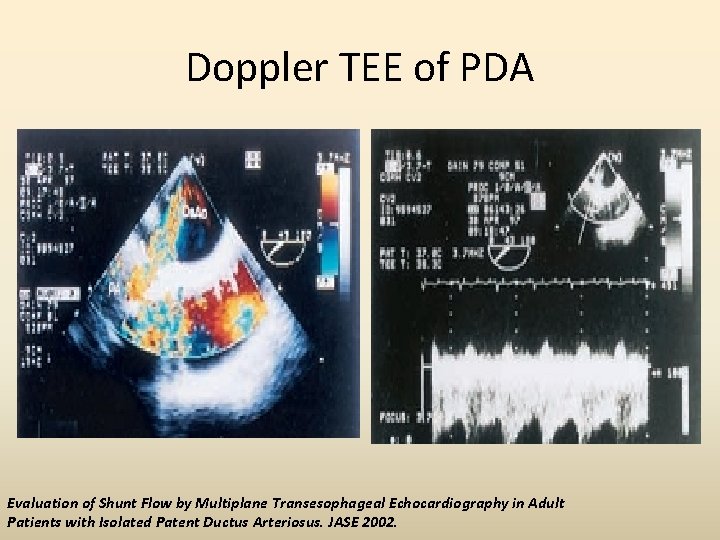

Doppler TEE of PDA Evaluation of Shunt Flow by Multiplane Transesophageal Echocardiography in Adult Patients with Isolated Patent Ductus Arteriosus. JASE 2002.